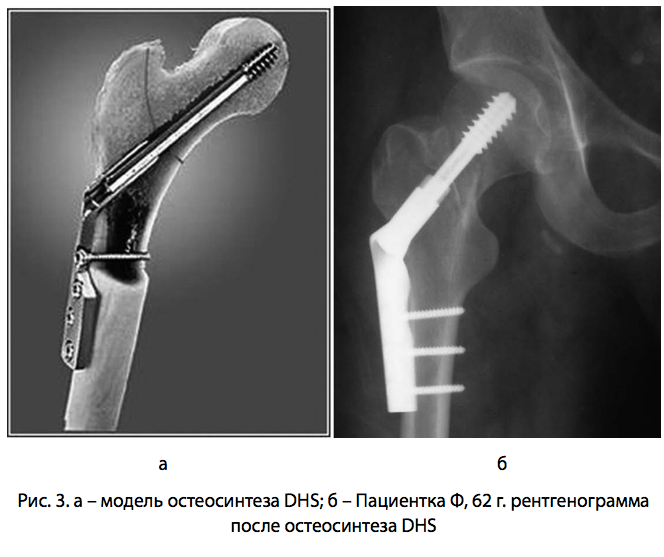

Широко распространен в лечении переломов шейки бедренной оксти остеосинтез динамическим бедренным винтом (Dynamic hip screw — DHS). Особенность данного винта заключается в его способности «пружинить». Так называемая моноаксиальная динамизация по оси шейки бедра обусловливает динамическую компрессию линии перелома, необходимую для костной консолидации. Винт закрепляется с помощью экстрамедуллярной пластины, расположенной на наружной поверхности бедренной кости, что обеспечивает фиксацию шеечнодиафизарного угла (Ананко А.А., Бабко А.Н. 2007).

Рис. 3.модель рентген

Однако при применении динамического бедренного винта у пациентов с внутрисуставными переломами шейки бедра положительный результат был достигнут только в 73,4% случаев (Majernicek M. et al. 2009). Следует отметить, что помимо стандартных осложнений остеосинтез DHS в некоторых случаях может сопровождаться миграцией винта и смещением костных отломков (Hrubina M., Skotak M. , Behounek J. 2010). Также существует очень вероятность ротационного смещения, учитывая отсутствие в конструкции деротационного компонента. Хотя система DHS активно применяется у больных с переломами вертельной области, исследований, посвященных лечению внутрисуставных переломов шейки, недостаточно для подтверждения его эффективности у данных больных.